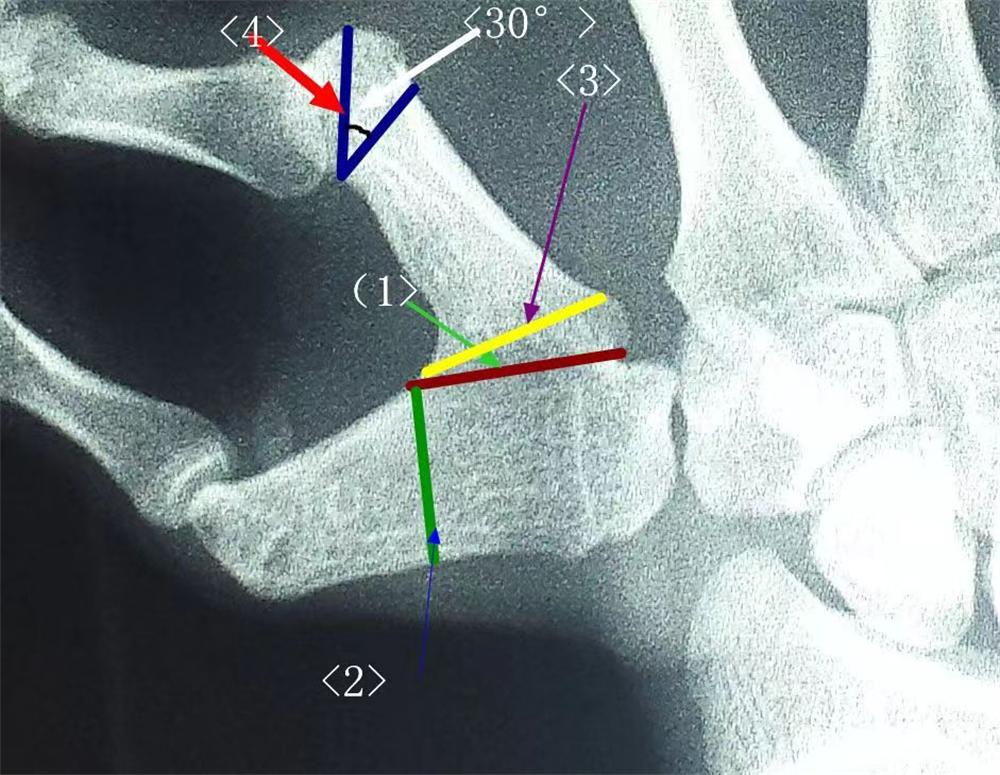

术前,袁重玺医师利用手术模拟系统仔细测量乐乐两个大拇指周径、长度和截骨角度等,并进行手术规划和预测,演示不同角度的术后效果,根据有关数据画出手术设计效果图。